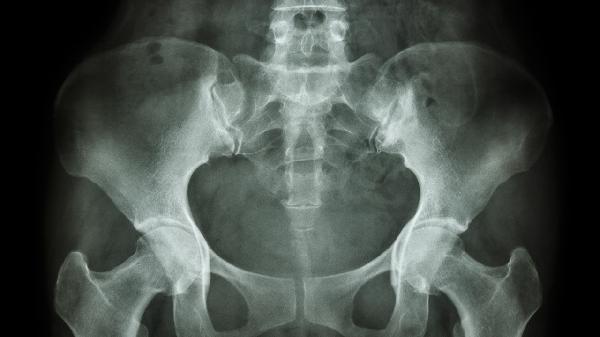

骨盆结核可通过抗结核药物治疗、手术治疗等方式治疗。骨盆结核通常由结核分枝杆菌感染引起,主要表现为局部疼痛、活动受限等症状。

对于出现严重骨质破坏、脓肿形成或神经压迫的骨盆结核患者,可能需要手术治疗。常见手术方式包括病灶清除术、植骨融合术等。手术能够清除坏死组织、引流脓肿、稳定骨盆结构。术后仍需继续抗结核药物治疗,防止结核复发。手术风险包括感染、出血、神经损伤等,需要由经验丰富的骨科医生操作。

急性期骨盆结核患者需要卧床休息,减少骨盆负重,必要时使用骨盆带或支具固定。这有助于减轻疼痛,防止病理性骨折和畸形加重。随着病情好转,可在医生指导下逐步恢复活动,进行适度的功能锻炼,防止肌肉萎缩和关节僵硬。

骨盆结核可能并发寒性脓肿、窦道形成、病理性骨折等。需要密切观察病情变化,及时发现并处理并发症。对于寒性脓肿,可考虑穿刺抽吸或切开引流。形成窦道者需要加强局部换药,保持引流通畅。发生病理性骨折时可能需要外固定或内固定治疗。

骨盆结核患者应注意保持乐观心态,积极配合治疗。治疗期间要定期复查X线、CT等影像学检查,评估治疗效果。日常生活中要注意个人卫生,避免劳累,保证充足睡眠。饮食上要均衡营养,戒烟限酒。家属应给予患者心理支持,帮助其坚持完成全程治疗。如出现发热、疼痛加重等情况应及时就医。